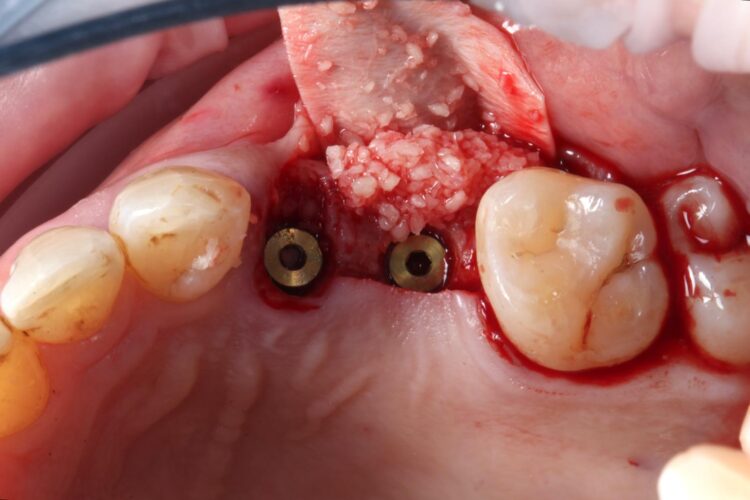

A flap was raised in the UL5 site using a paracrestal incision – vertical incisions were avoided to preserve blood supply to the gingiva, protecting the papilla between the UL6/7 for optimal aesthetic and soft tissue outcomes.

Technically, a flap is not typically needed for many immediate implant cases. However, as the UL5 site needed augmentation and mild atrophy of the ridge was present. The clinician does not advocate flapless procedures for implant placement due to the need to see the underlying ridge and implant following placement.

The surgical guide was then placed in the mouth and the manufacturer’s specific drilling sequence followed, increasing the osteotomy in size incrementally.

Two 3.8mm diameter CONELOG® Progressive-Line implants were placed through the guide, following the plan precisely. The UL4 implant was longer (11mm) to ensure sufficient apical bone was engaged for primary stability, it was also positioned in the palatal root to ensure good engagement with the bone and better bone to implant contact. A sizable jump gap was noted between the implant and the buccal plate of around 5-6mm. From a biological perspective, the jump gap can be left because the ridge would heal to leave a sufficient buccal plate. However, the literature[iv] shows that grafting reduces the amount of bone resorption post implant placement, which was one of the reasons that augmentation was indicated in this case.

Another predetermined concern was the amount of remaining bone surrounding an implant after placement. There was less than 2mm of residual bone buccal to the UL5 site once the implant was placed. Alberto Monje et al. (2023) [v] showed that thin buccal bone at the implant site increases the risk of major dimensional changes, this can have direct implications on the aesthetics and functional outcomes.

Consequently, the bone was contour-augmented, using MinerOss® Blend (BioHorizons Camlog), which provides a good combination of cortical and cancellous bone for efficient bone turnover and also maintains graft stability in the healing phase. The graft was held in place with a collagen membrane stabilised using resorbable sutures. The custom healing abutment is then placed and torqued (10Ncm) into the UL4 implant before the wound is approximated and sutured using a non-resorbable 6-0 Prolene suture.